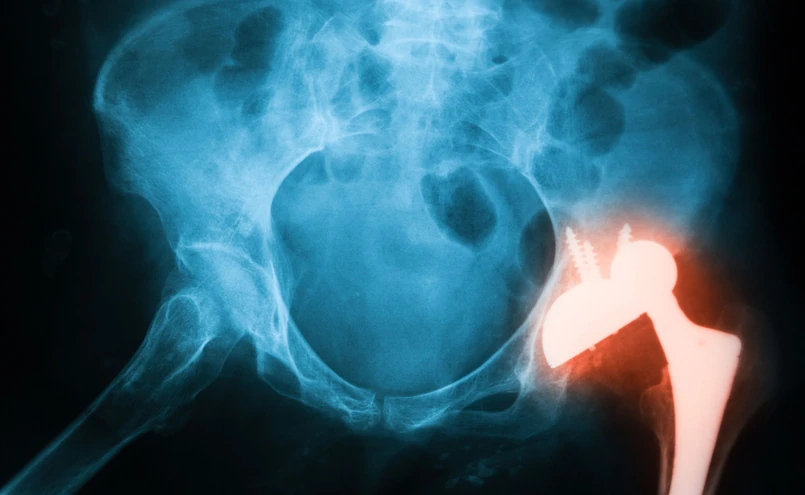

Implant stawu biodrowego, endoproteza

Zmiany na rynku implantów ortopedycznych w Polsce: MedTech Solutions z wyłącznością na implanty GPC Medical/Shutterstock